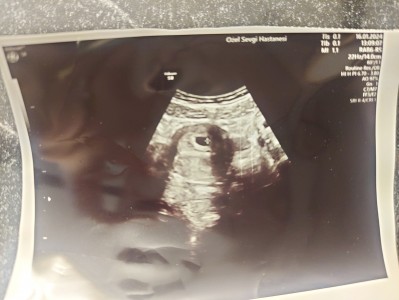

Kizlar 5+3 hamileyim bugun ilk defa kontrole gittik. Çok şükür kese var kese büyüklüğü haftasiyla denk ama bebegı göremedim.doktorda bisey demedi.15 gün sonra kalp atışı için gel dedi.nisan ayinda bir kaybim oldu o yüzden evhamlıyım biraz. Ama çok şükür iyi dedi doktor değerleri. Sizce normalmi ?

Gebelik haftası 5+3